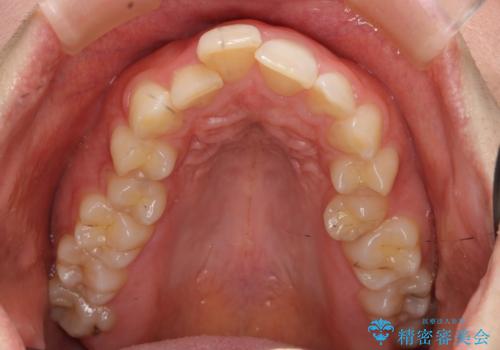

- 前歯のがたがたと出っ歯を主訴に来院。

CTを撮影したところ、臼歯部の頬側の骨の厚みが非常に大きく、通常では考えられない量の歯列の拡大が可能でした。

今回は健康を損なわずに非抜歯で治療が可能でしたが、

歯ぐきや骨の厚みが薄い他の患者さんでは難しいです。

左上5は180度捻転していましたので、そのまま並べています。

遠心移動などは行わず、IPRと拡大のみで治療を行いました。